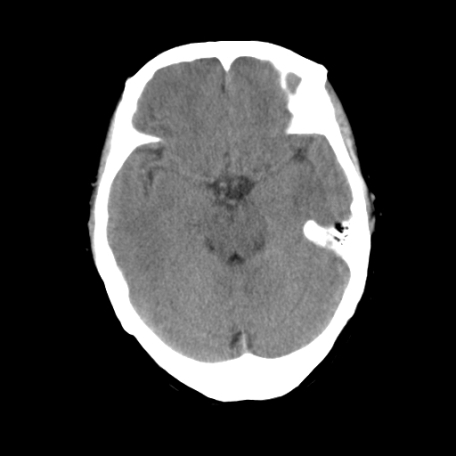

以下是引用深泽交通医院在2009-8-7 12:18:00的发言:[br]有壁结节,考虑囊变型胶质瘤

以下是引用帅河马在2009-8-7 13:50:00的发言:[br][quote]以下是引用深泽交通医院在2009-8-7 12:18:00的发言:[br]有壁结节,考虑囊变型胶质瘤

以下是引用卜一在2009-8-7 15:50:00的发言:[br]囊变性脑膜瘤!支持!

以下是引用随光逐影在2009-8-7 15:58:00的发言:[br]考虑左侧顶叶胶质瘤,不排除左侧镰旁脑膜瘤;建议行进一步检查。

以下是引用shibing在2009-8-7 16:36:00的发言:[br]增强扫描